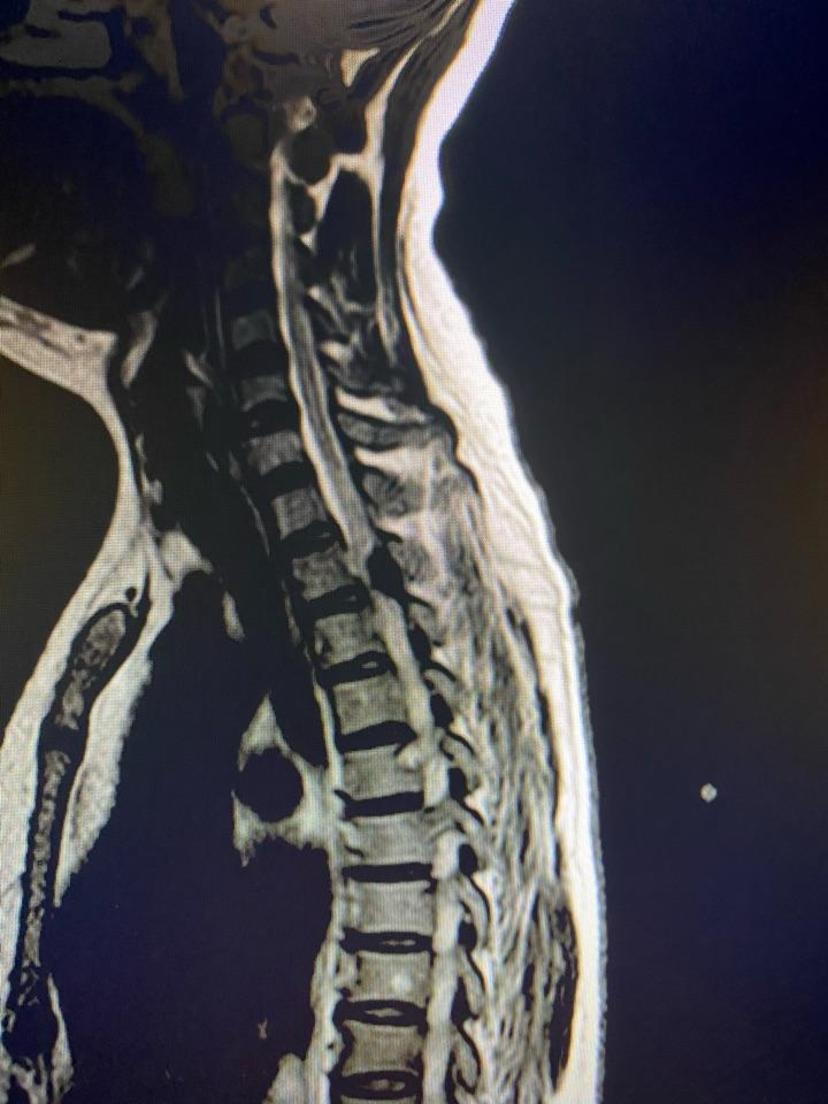

胸椎磁共振显示胸2-3平面黄韧带骨化物压迫脊髓ct显示骨化物占满整个

图片尺寸828x1104